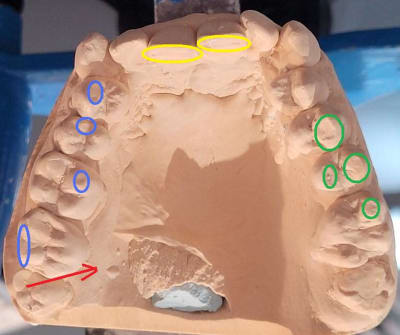

Je fais suite avec l'OIM que je trouve. a priori, Déviation a gauche. Serait ce pour repositionner L'atm droite ou pour éviter une gêne a droite ? (en rouge rapport sur articu )

donc il y a une 18 en fer .

au vu de l usure , cette couronne exerçait un poussée de la mand vers la gauche . trait rouge .

en 2016 la cc etait moins usée le décalage etait donc plus fort .

la mand etait quand même un peu calée déportée à gauche , bien qu il existait une grande instabilité de calage pcq les points sont pointe contre pointe .ronds verts et bleu .

deja elle avait l habitude d augmenter sa stabilité en se positionnant devant . ronds jaunes .